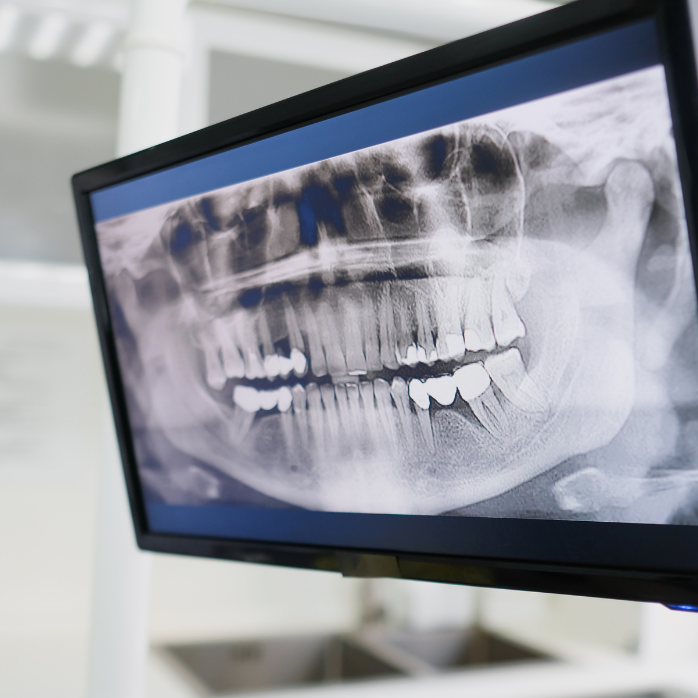

RTG zubov je zobrazovacie vyšetrenie, pri ktorom sa pomocou röntgenového žiarenia vytvorí snímka zubov, koreňov zubov, čeľuste a okolitej kosti. Na snímke možno vidieť aj skryté problémy, ako sú napríklad začínajúce kazy medzi zubami, zápaly pri koreni zuba alebo zmeny v kosti.

Naše zubné ambulancie sú vybavené RTG ale aj OPG. To znamená, že sme schopní Vám urobiť malý snímok (RTG) ale aj veľký snímok (OPG), všetko na jednom mieste. Snímky robíme každý Utorok a Štvrtok od 12:00 do 13:00.